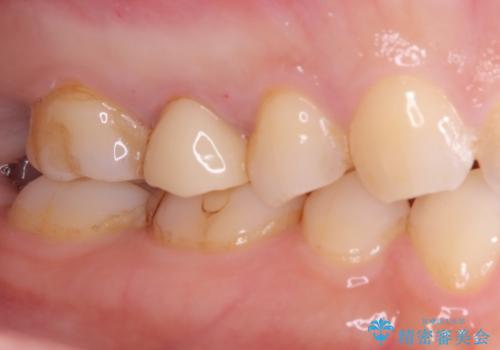

【オールセラミッククラウン】根管治療も行いたい。

- 右上の歯が、噛むと痛いことを主訴に来院されました。

ラバーダムと顕微鏡を用いた根管治療を希望され、治療後は痛みも改善することができました。

その後、オールセラミッククラウンにて修復を行っています。

顕微鏡を用いて根管治療を行うことで、破折の有無などを判断しやすくなります。